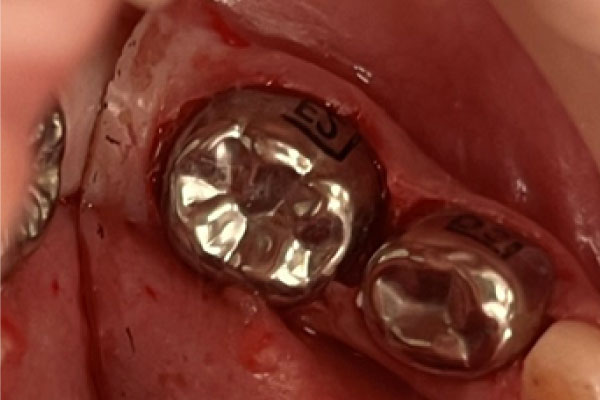

Примеры лечения зубов

Лечение пульпита/периодонтита

Восстановление жевательного зуба после эндодонтического лечения